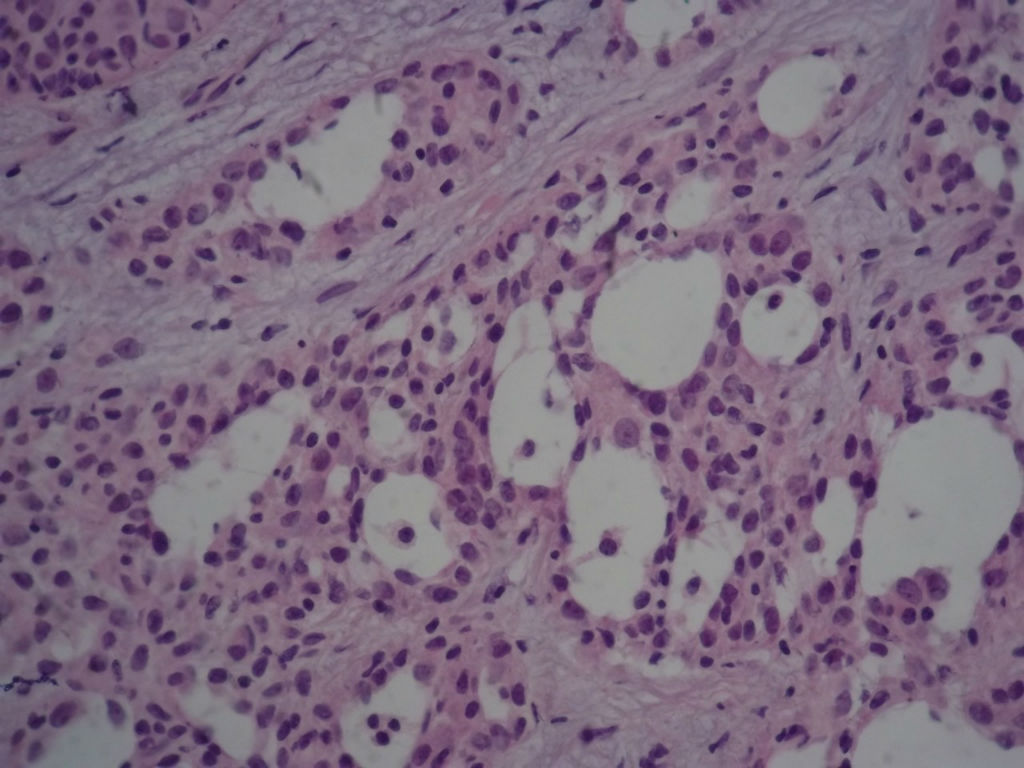

本例太完美了,也非常惊险,真的,至少在我们中国的这个病理环境下能做到这样真心不错。这是个罕见病例,居然冰冻让你碰上了,从冰冻——常规——IHC都完备。我从冰冻看到常规未看免疫组化之前还一直犹豫是不是癌?是癌但一定是您说的分泌性癌吗?看常规时只是觉得浸润性癌够了,后来看到常规的筛状结构+分泌物才确定形态学也够了,就差IHC了,结果您贴出来上级医院的IHC结果真的是3阴,S-100+,高分子量CK部分+,这个表达模式完全符合分泌性癌(我也遇到一个分泌性癌,IHC表达方式完全和您的这例一样),当然必须是结合形态学了。

Secretory breast carcinomas (o0.15% of breast tumors) are associated with a characteristic morphology and a

favorable prognosis. Remarkably, this entity is the only epithelial tumor of the breast with a balanced

determine the phenotypic class (ie luminal A/B, ERBB2, basal-like) of secretory breast carcinoma. A series of six

antibodies. In situ and invasive components shared the same immunoprofile and were ER, PR, ERBB2 negative

with expression of basal cytokeratins. ETV6 gene alterations were present in both in situ and invasive

components, highlighting their genetic similarities. The immunoprofile data (triple-negative with expression of

basal markers) showed that secretory breast carcinomas with ETV6-NTRK3 fusion gene belong to the

phenotypic basal-like spectrum of breast carcinomas. These results support the hypothesis that secretory

breast carcinomas have immunohistochemical and genetic features that distinguish them from other basal-like

tumors of the breast.